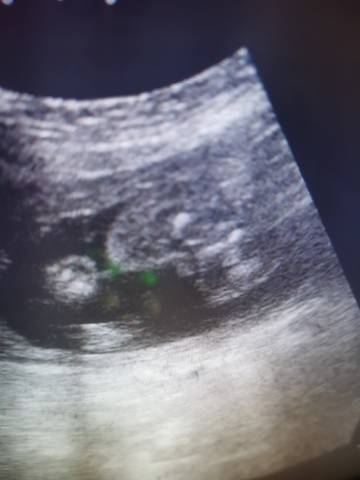

谁能看看这是个啥,看的出来是男孩还是女孩不

你好,从这个图片上看不出宝宝的性别,不管宝宝是男孩还是女孩,只要宝宝健健康康就好,祝你心想事成。

通过这些是看不出来的,而且也不准确,在怀孕期间,我觉得只要宝宝发育好的话,还是不要想太多了,男孩女孩都一样的。

亲爱的,通过这些判断不出来是什么样性别的哈,反正宝宝发育好就是最好的哈,祝你好孕。

你好。我们是判断不了男宝宝跟女宝宝的,孕期定期检查,我觉得宝宝健康就好的。祝心想事成 。